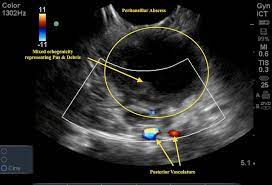

Here are some breast cancer ultrasound images: In most cases, throat cancer originates in the flat cells that line the inside of the throat, a muscular tube that extends from the nose to the bottom of the neck. The ultrasound images are then projected onto a computer screen. The outlook depends, to some extent, on where cancer starts. An ultrasound may show your doctor if a lump is filled with fluid or if it's solid.

While it can't diagnose cancer, it can detect the abnormal tissues that may possibly be cancerous. The cells are then looked at closely in the lab. Staging head and neck cancers An ultrasound may show your doctor if a lump is filled with fluid or if it's solid. If the cancer cells look like they might have come from the larynx or hypopharynx, an endoscopic exam and biopsy of these areas will be needed. When the thyroid becomes damaged, it stops producing thyroid hormone (hypothyroidism). Throat cancer can develop in any part of the throat. Ultrasound imaging can help determine the composition of lump, distinguishing between a cyst and a tumour. And if this isn't cancer, could anybody offer an explanation as to what would cause a sore throat and growing lump? It can detect abnormal tissues, growths, and cysts and give a suspicion of cancer based on how those images look. What does ovarian cancer look like on an ultrasound is not an easy question to answer. Some symptoms of throat cancer are specific to certain areas of the body. Effective treatment is possible in many cases.